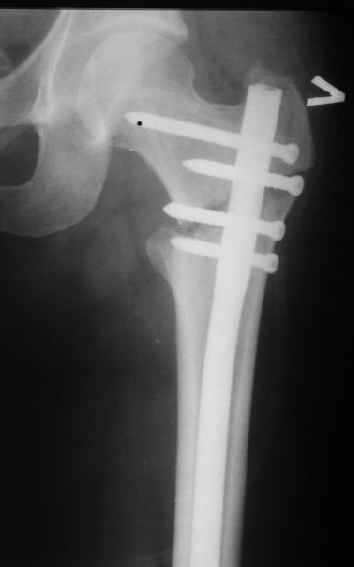

В частности, на проксимальном конце сделано еще одно дополнительное статическое отверстие. Можно ввести в проксимальном отделе 4 винта, из них 3 статические (2 в круглые отверстия и 1 по нижнему краю овального). Картинки в приложении. На дистальном конце стержня тоже кое-что улучшено. Спрашивайте в аптеках, как говорится. Выпускается предприятием "ЦИТО" (Москва), то есть это малобюджетное решение.

Конечно, мы не синтезируем остеопорозые вертельные переломы согласно прилагаемому примеру, винты 6 мм вырежутся. Но у более молодых при хорошем качестве кости такие или подобные гвозди с поперечным расположением винтов вполне применимы для меж- и подвертельных переломов.

Женя, эта картинка показывает не оптимальное лечение вертельных переломов в моем представлении, а особенности дизайна упомяутого фиксатора.

В частности, его возможности при фиксации переломов проксимального отдела бедра - в сравнении с другими, имеюшими лишь по одному статическому и динамическому отверстию и с кондуктором для введения 2 винтов.

Это было года 2,5 назад, мы тогда еще уточняли возможности шинирования с угловой стабильностью гвоздем с поперечным расположением винтов при переломах проксимального отдела бедра. Пациенту не пришлось приобретать намного более дорогой рекон или проксимальный гвоздь. В приложении еще несколько примеров применения того гвоздя при высоких переломах бедра, в том числе с более латеральной точкой входа. Гвоздь изгибаем для этого.